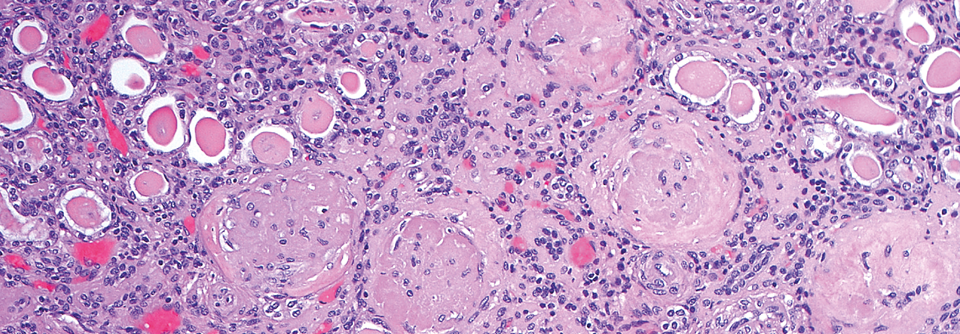

Bei Typ-2-Diabetes-Patient:innen wird das kardiovaskuläre Risiko in vier Klassen eingeteilt. Bei Typ-2-Diabetes-Patient:innen wird das kardiovaskuläre Risiko in vier Klassen eingeteilt. © WindyNight – stock.adobe.com